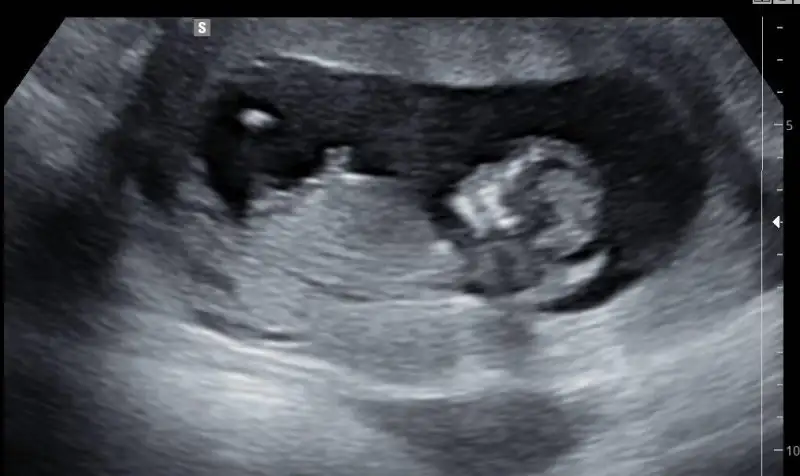

nub teorisi var canim resim at bakalim nasil

Eklentiler

• 1.webp

1.webp

25,3 KB · Görüntüleme: 76